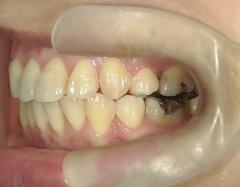

矯正歯科(全顎ワイヤー矯正)治療後

矯正歯科 治療後